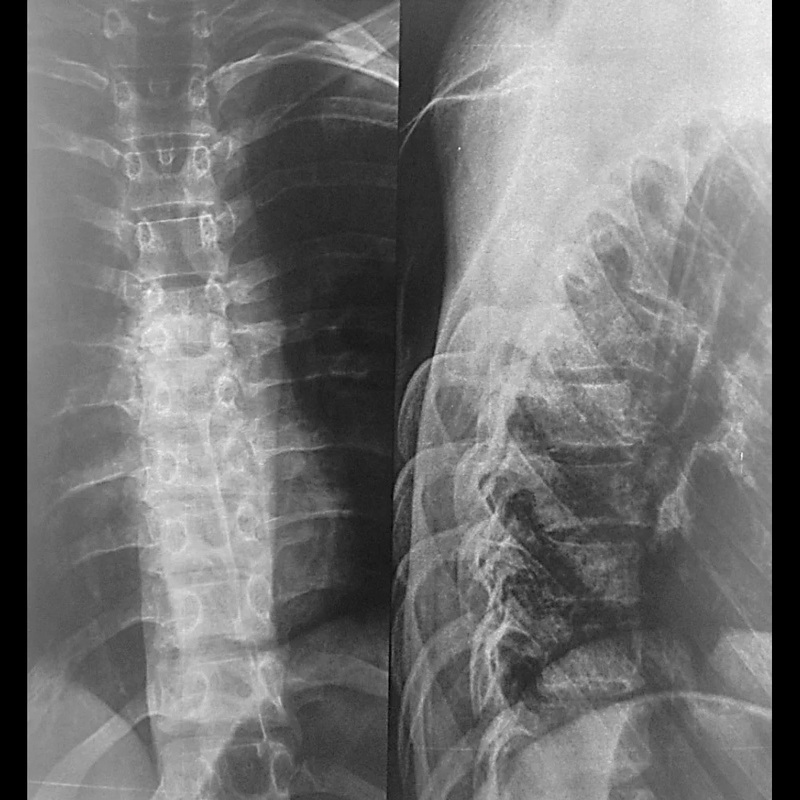

Рентген поясницы: анатомические особенности и медицинские исследования

Раздел: Фотоэссе